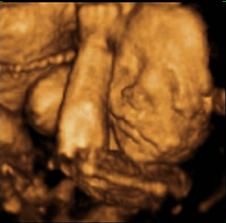

4.11.2011 3D ultrazvuk a konečne sme sa dozvedeli pohlavie - Je to dievčatko, aj napriek tomu, že sme boli všetci presvedčení, že to bude chlapček. Ale s nami vybabrala, zlatinko naše 🙂